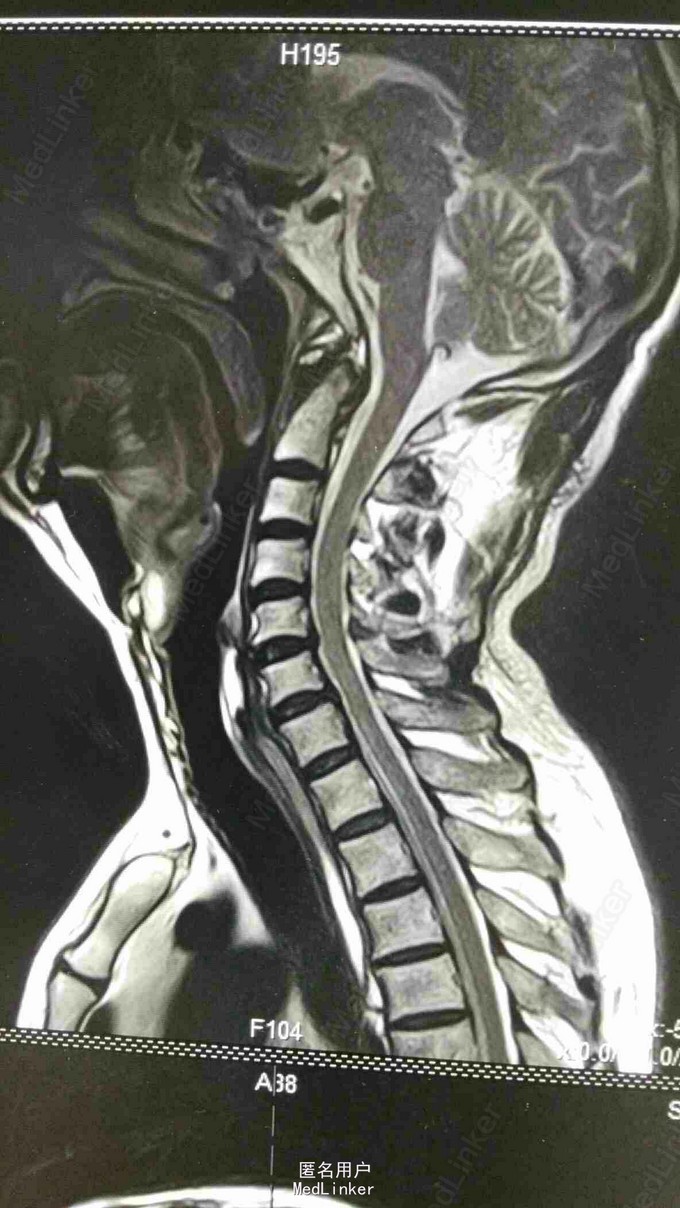

脊柱序列如常,生理曲度存在,未见后凸及侧弯畸形。颈椎前屈、后伸、侧屈及旋转功能无明显受限,颈3-7椎间隙及棘突旁压痛。腰椎棘突及椎旁压痛,右小腿内侧皮肤感觉较左侧减退。

第一诊断:脊髓型颈椎病; 第二诊断:腰椎间盘突出症。 治疗:颈椎棘突间电针刺激每日一次,并针对颈腰椎进行按摩、熏蒸。 中药口服:半夏(清半夏)9g,生白术12g,天麻9g,柴胡12g,三棱9g,莪术9g,党参12g,黄芪15g,炒山药15g,陈皮6g,茯苓12g,生甘草6g。

患者出院后门诊随访,近期患者自觉头晕恶心等症状基本缓解,右下肢力量有所增强,活动改善。嘱其避免劳累及受凉。 电针刺激进针位于颈3到颈7的棘突之间,进针深度3.5公分。口服中药行补气活血,降逆去湿的作用。出院后颈肩背部嘱其在家中中药热敷以巩固疗效。